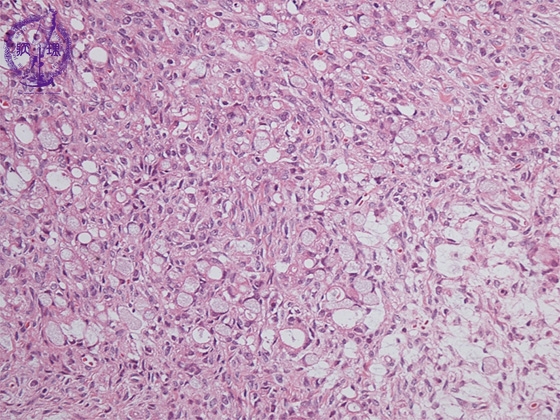

- ★(12)Krukenberg tumor

Histology (HE stain, low power): Signet-ring cell carcinoma proliferated with scattering pattern (light blue). Fibroblasts demonstrated reactive proliferation in interstitium.